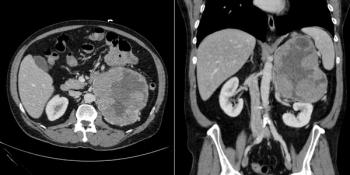

A 56-year-old woman presents with abdominal fullness and virilization. Axial and coronal images from a CT scan of her abdomen are shown below. What is your diagnosis?